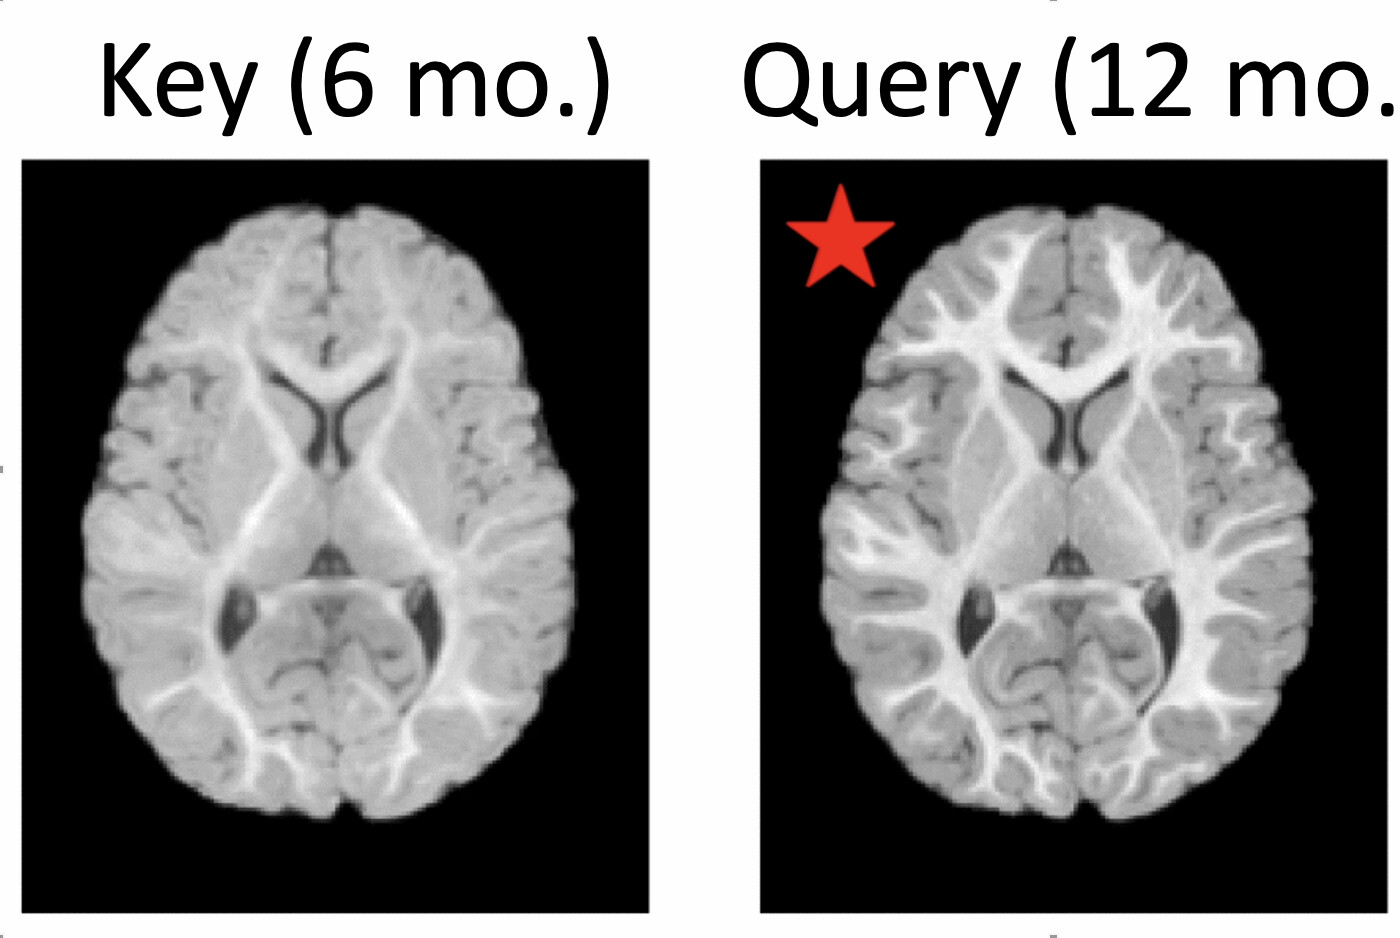

Local Spatiotemporal Representation Learning for Longitudinally-consistent Neuroimage Analysis

NeurIPS (oral) 2022

Mengwei Ren, Neel Dey, Martin A. Styner, Kelly N. Botteron, Guido Gerig

A local and multi-scale spatiotemporal representation learning method for image-to-image architectures trained on longitudinal images.